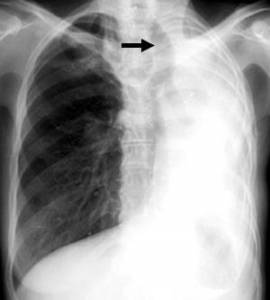

- Рентгенография грудной клетки.